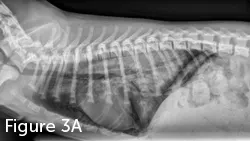

A lateral radiograph of a canine thorax shows the skeletal structure, including the ribs and vertebrae, with clear visualization of the heart and lungs. The image highlights the overall anatomy and potential abnormalities within the thoracic cavity.

FIGURE 3

Lateral (A) and VD (B) thoracic radiographic views of a dog with NCPE. Note the focal interstitial to alveolar pattern present in the 3 caudodorsal lung fields.

Diagnosis of NCPE is often based on history, examination, and radiographic imaging. Classic radiographic findings include increased interstitial or alveolar opacity, notably in the caudodorsal lung fields (Figure 3). This contrasts with radiographic findings in patients with cardiogenic pulmonary edema, notably perihilar edema. However, other forms of respiratory disease should be investigated, including cardiogenic pulmonary edema, pneumonia, and hemorrhage from trauma or coagulation abnormalities. Echocardiography can exclude cardiogenic edema and left-sided heart failure. A coagulation profile should be performed and pneumonia ruled out based on history, physical examination findings (eg, nonfebrile), and CBC results.